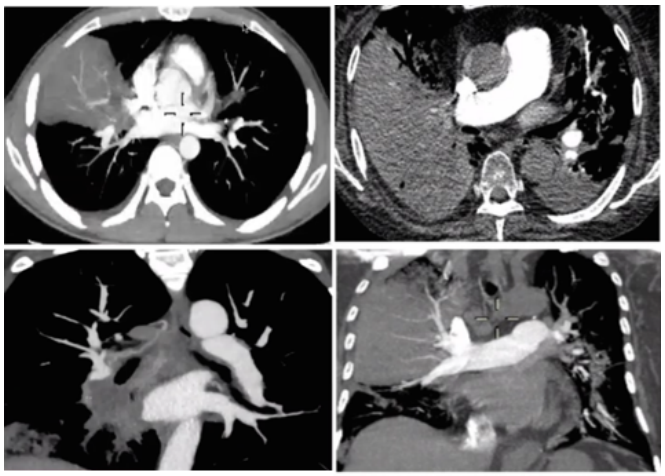

相关文献报道很少,涉及8例流感病毒相关毛霉病(IAM)和7例新型冠状病毒相关毛霉病(CAM)。笔者总结了这些患者的临床特点:①平均年龄为55岁,所以IAM/CAM可能与高龄无关;②男性发病居多,占73.3%,其中IAM发病率为62.5%,CAM发病率为85.7%;③存在至少一种除病毒感染外的基础病;④严重程度(重度);⑤危险因素:糖皮质激素,粒缺,高血糖;⑥毛霉病类型:IAM(肺毛霉病),CAM(鼻-眶-脑型毛霉病);⑦毛霉病诊断距病毒性肺炎时间:平均16.3天,偏晚。IAM/CAM的影像学相对特异,包括反晕征、厚壁空洞、大片实变伴支气管截断征(毛霉多导致支气管截断、破坏,曲霉多为支气管壁增厚、狭窄)等(图8,图9)。此外,增强CT/CT肺动脉造影(CTPA)对于毛霉病的诊断也非常重要,尤其是诊断假性动脉瘤—真菌性血管瘤,以及发现血管受侵(毛霉多侵犯大中血管)(图10,图11)。在上述15例患者IAM/CAM患者中,手术比例达到50%,大多采用了单药或联合抗真菌治疗,但病死率仍然高达66.7%,IAM病死率为37.5%,CAM患者病死率甚至达到100%。(1)危险因素:高龄可能并非病毒合并毛霉病的高危因素(平均55.7岁);男性发病更常见(73.3%);糖尿病、酸中毒、糖皮质激素是其危险因素。